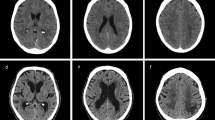

(A) The dose–response relationship between postoperative mean PP and unfavorable prognosis at 3 months through restricted cubic splines (RCS) with 3 knots. (B) The dose–response relationship between postoperative mean PP and unfavorable prognosis at 12 months. (C) The dose–response relationship between postoperative mean PP and mortality at discharge. (D) The dose–response relationship between postoperative mean PP and mortality at 3 months. (E) The dose–response relationship between postoperative mean PP and mortality at 12 months. (F) The dose–response relationship between postoperative mean PP and symptomatic intracerebral hemorrhage.

Restricted cubic spline (RCS) with 3 knots was used to explore the relationship between postoperative PP and outcome variables after adjusting confounding factors in Fig. 2. Mean PP demonstrates a significant dose–response relationship with the occurrence of functional outcomes, sICH, and mortality after thrombectomy, with an increased risk of adverse outcomes as PP rises. Besides, mean PP exhibits a linear relationship with all other outcome events, except for mortality at 12 months post-EVT.